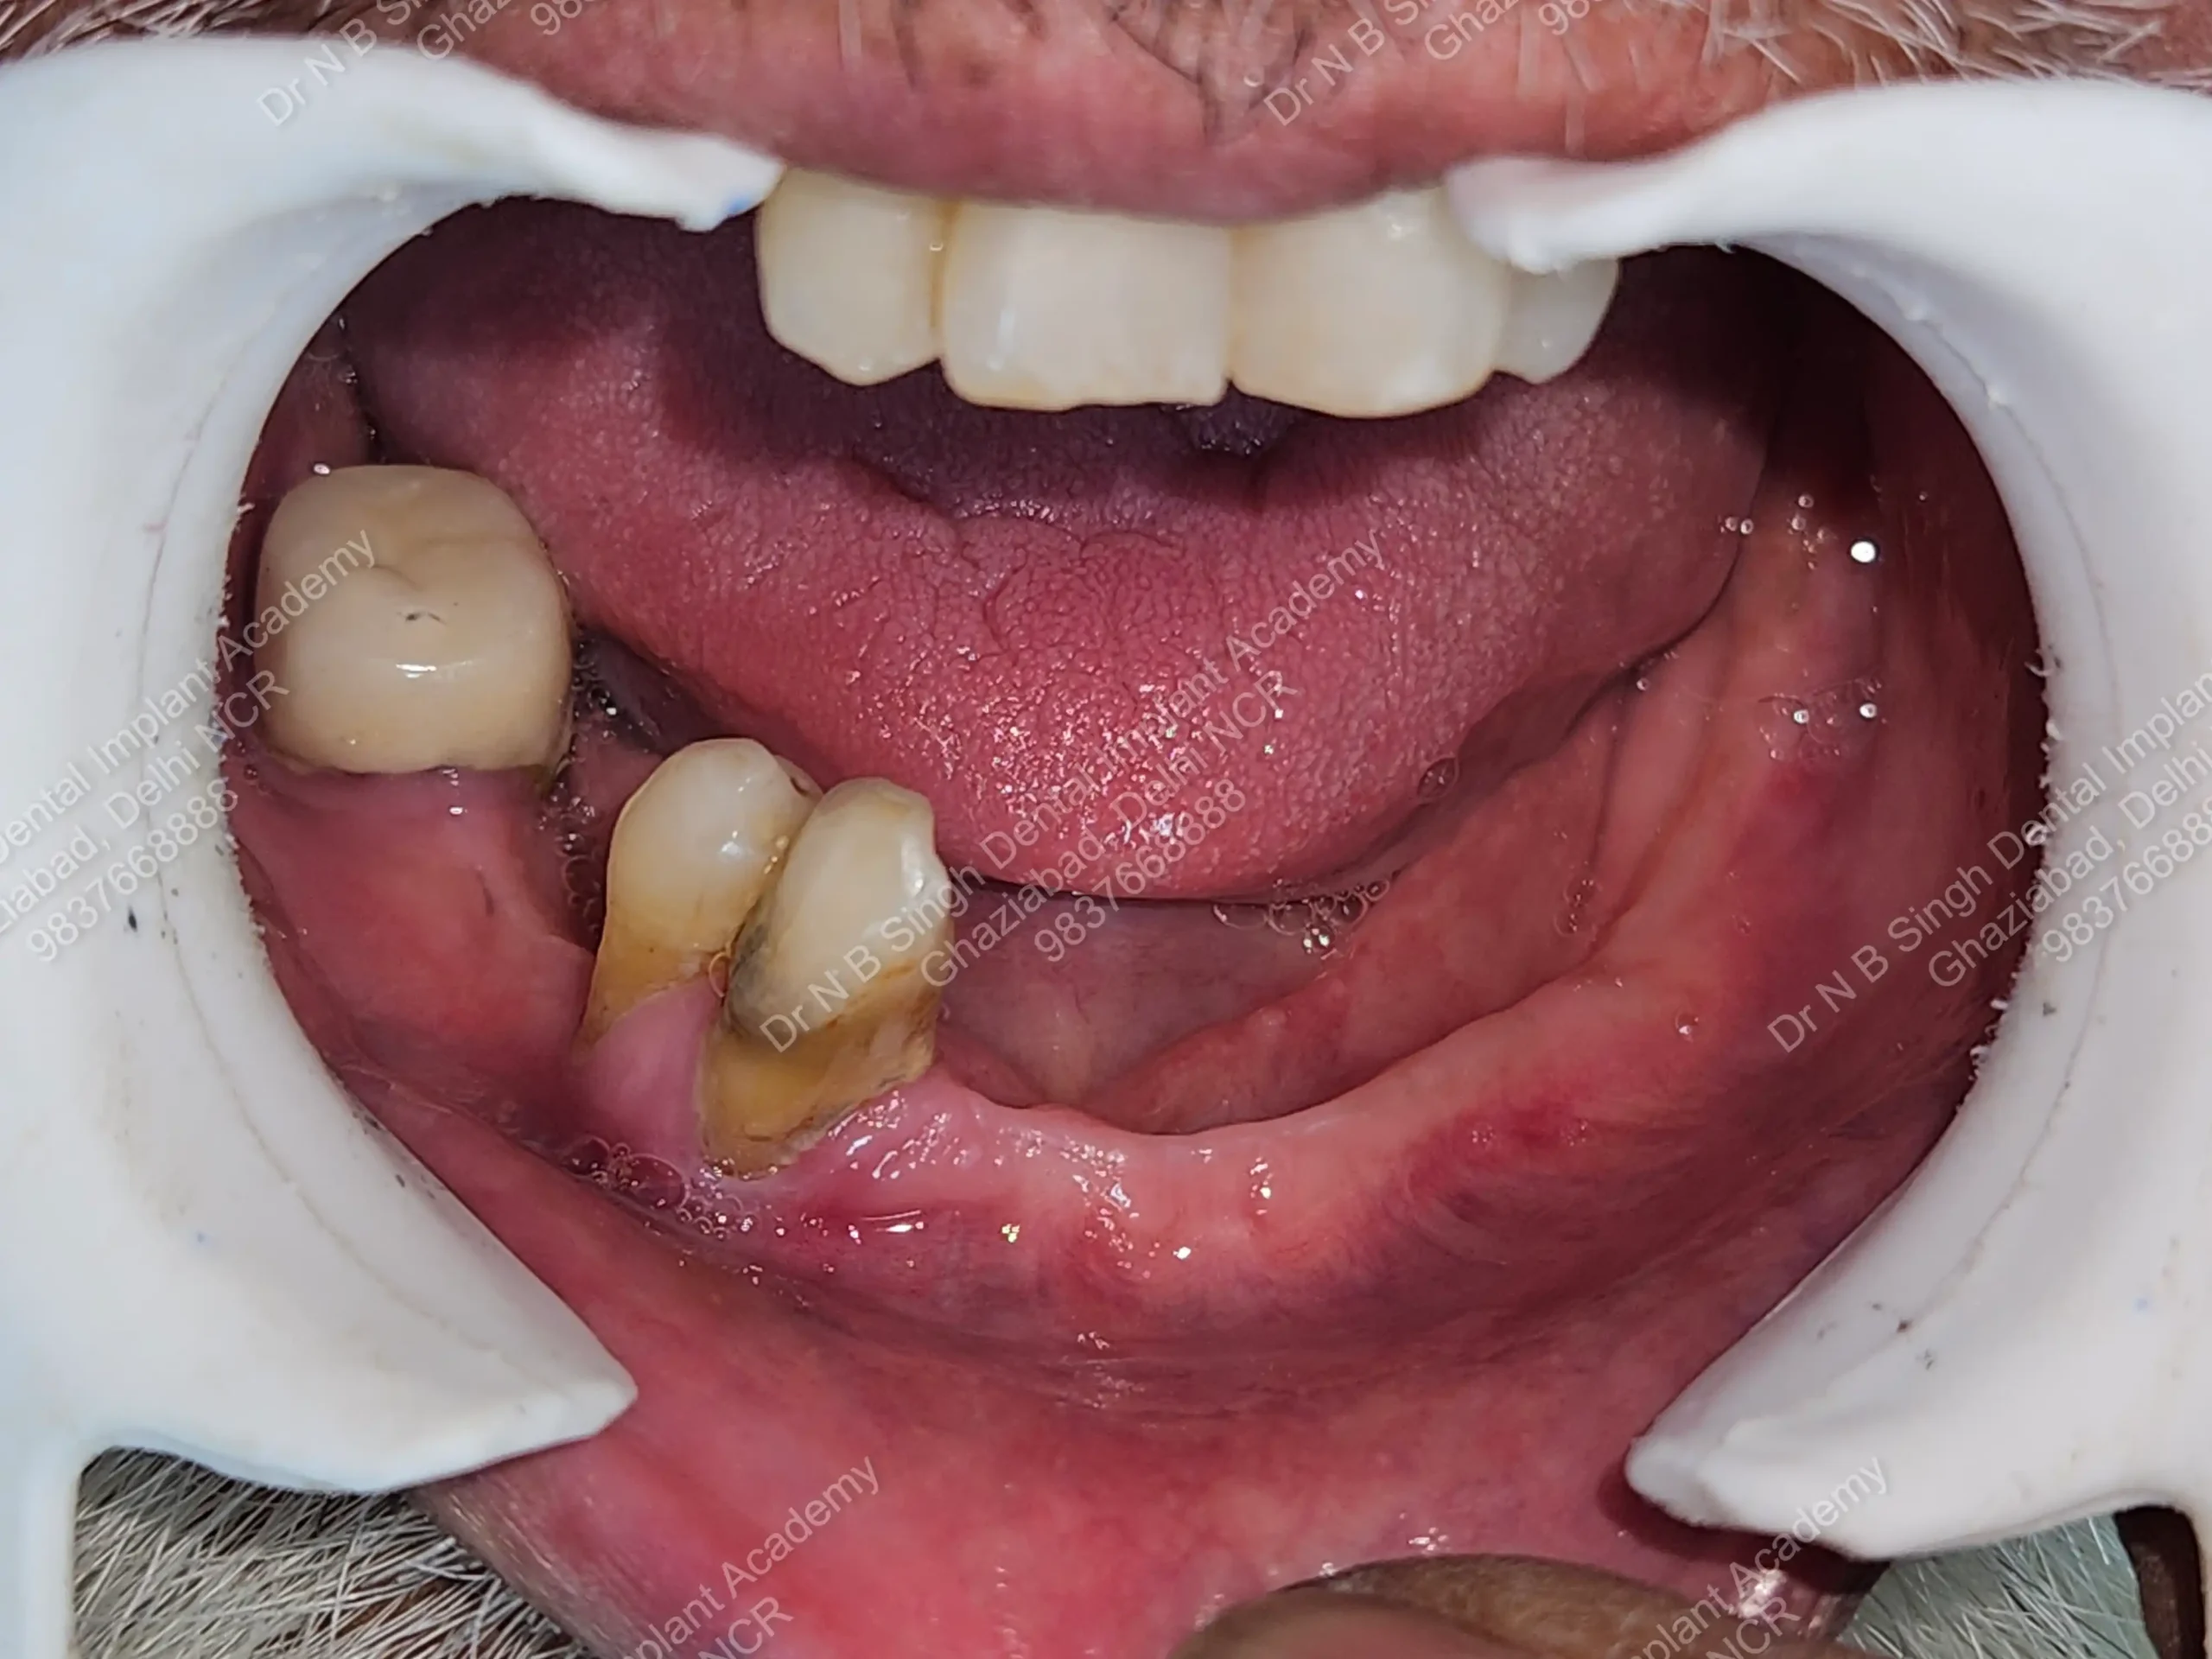

A008 Basal implants – af-qurs 1

Dr. N.B. Singh